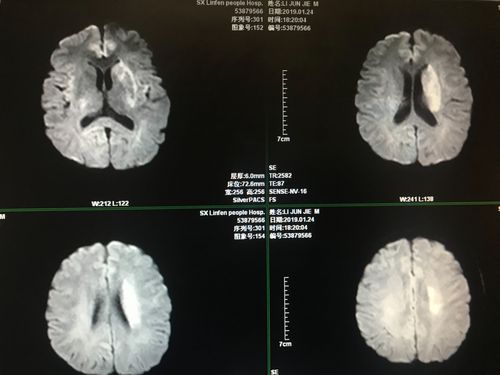

双侧侧脑室,侧脑室位置图片

mr:见左侧脑室旁脑梗塞.

约40%的病例为双侧轻度侧脑室增宽